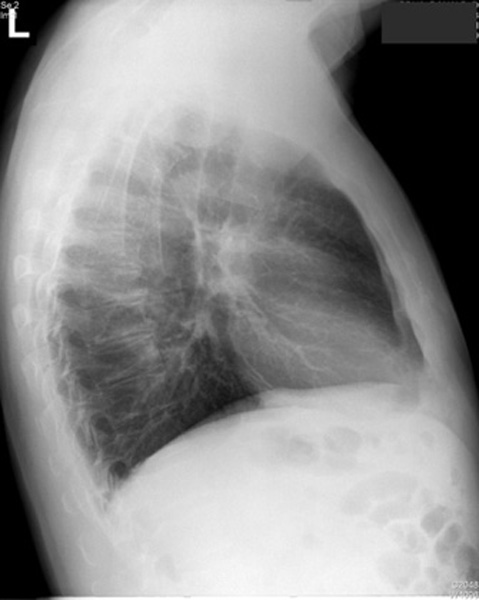

Interpretation